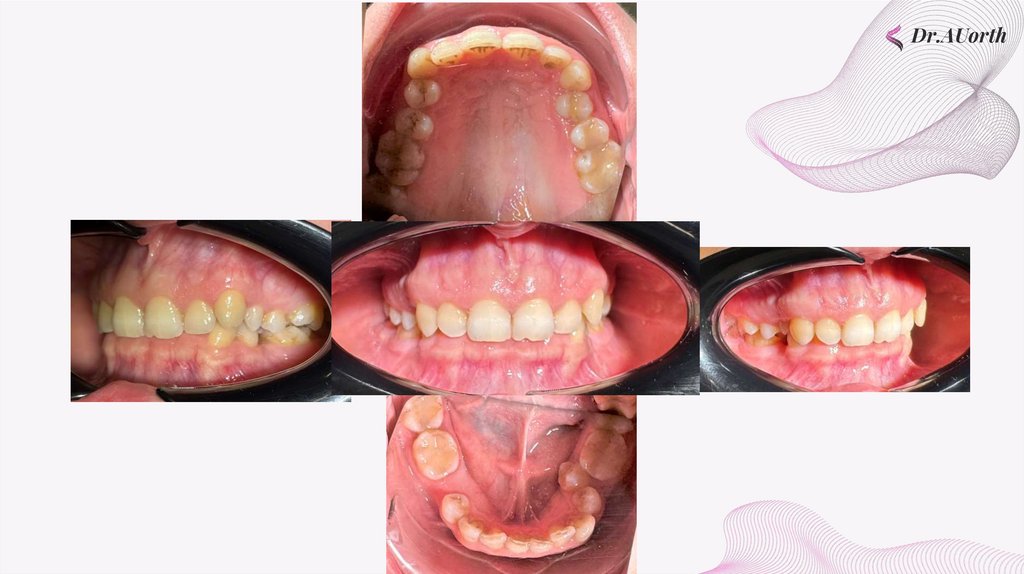

внутриротовые фотографии

Dr.AUorth

Второй класс по клыкам справа, второй - по клыкам слева.

Сагиттальная щель отсутсвует. Ретрузия резцов на нижней, верхней

челюсти

окклюзионные фотографии

Вторичная адентия зуба 3.5. Несоответсвиет Герлаха